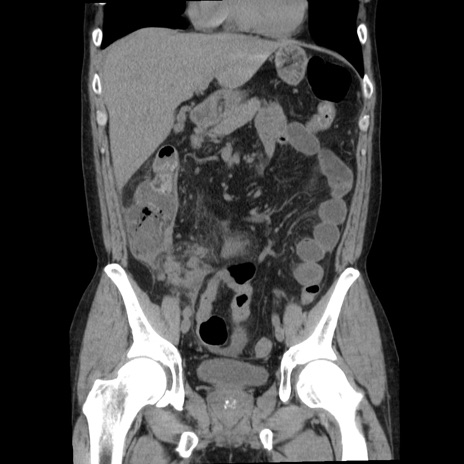

症例29(冠状断像)

【症例】40歳代男性

【現病歴】2日前から胃痛あり。徐々に周期的な激痛に変化した。本日になっても激痛があるため受診。

【身体所見】意識清明、BT 38-39℃台あり、腹部:膨満、やや硬、右下腹部に圧痛あり。

【データ】WBC 8500、CRP 23.26